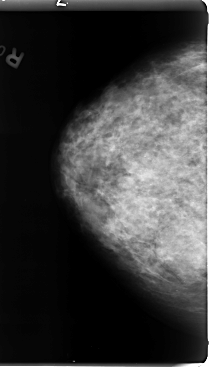

B_3082_1.RIGHT_MLO

B_3082_1.LEFT_MLO

LEFT_CC LINES 4720 PIXELS_PER_LINE 2864 BITS_PER_PIXEL 12 RESOLUTION 50 OVERLAY

LEFT_MLO LINES 4672 PIXELS_PER_LINE 2880 BITS_PER_PIXEL 12 RESOLUTION 50 OVERLAY

FILE: B_3082_1.LEFT_MLO.OVERLAY

TOTAL_ABNORMALITIES 1

ABNORMALITY 1

LESION_TYPE CALCIFICATION TYPE PLEOMORPHIC DISTRIBUTION CLUSTERED

ASSESSMENT 4

SUBTLETY 2

PATHOLOGY MALIGNANT

FILE: B_3082_1.LEFT_CC.OVERLAY